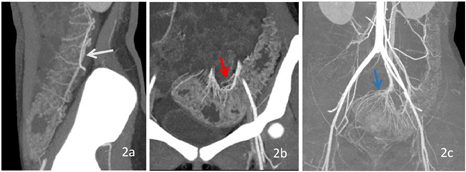

UC是一种非特异性慢性炎症性肠病,病因不明,易复发。诊断主要基于临床症状、实验室结果、内镜及组织学评估[1]。由于内镜是侵入性检查,部分患者无法忍受,且内镜检查无法观察肠外情况[2]。且对于不同分级、分期、病变部位的患者采用不同的治疗方法,准确诊断疾病对治疗及预后至关重要[3]。CTE可作为内镜检查的辅助检查手段,用于评估病变范围、分布、严重程度、病情分期、肠外情况及并发症[4]。CTE是采用双能量进行扫描,检查前患者饮用大量水,将肠腔充盈,有利于显示肠壁及腔内情况,在140kV下采集的CT图像较80KeV对比度增强,两者的融合图像对病变显示最佳(图1,图2)。同样的数据可用于进行MIP和CR后处理,不增加患者的辐射剂量,在MIP图像上,能够显示病变肠管周围的肠系膜血管,对"齿梳征"的显示更加清楚;在CR图像上能显示UC特有的"舞龙征"[5],有助于UC的诊断。骨结构可以通过syngo.CT Direct Angio去除,以清晰显示血管和病变肠管(图4b)。所有这些应用程序都是在自动化的工作流中执行的。